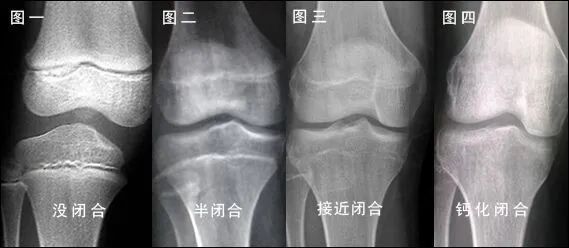

有呀。一般小朋友要長(zhǎng)高,骨骼生長(zhǎng)功不可沒,長(zhǎng)骨的兩端存在著非常特殊的區(qū)域——骨骺和生長(zhǎng)板,骨骼變長(zhǎng)就是通過這一區(qū)域的生長(zhǎng)來實(shí)現(xiàn)的。同時(shí),隨著年齡的增長(zhǎng),骨骺的生長(zhǎng)逐漸緩慢,生長(zhǎng)板逐漸變薄,最終完全與骨骺融合后便不會(huì)生長(zhǎng),人也就不能繼續(xù)長(zhǎng)高。因此,我可以用來判斷骨的發(fā)育程度,預(yù)測(cè)兒童的成年后身高,此外還能為某些內(nèi)分泌疾病、營(yíng)養(yǎng)障礙的診斷提供參考。